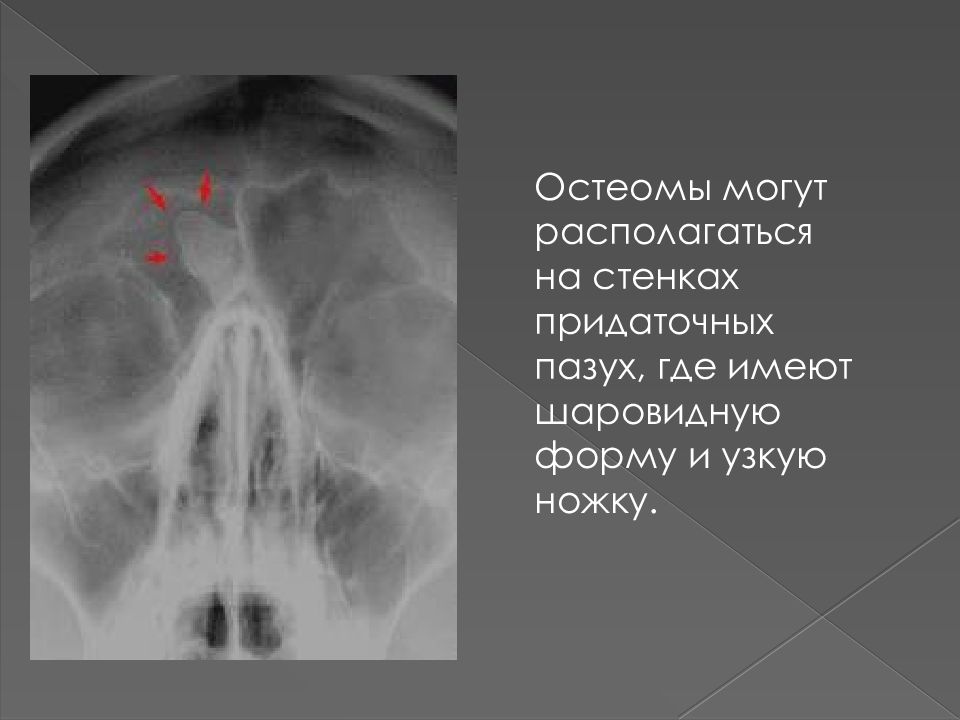

КТ околоносовых пазух. Что такое остеома?

Остеома пазухи носа